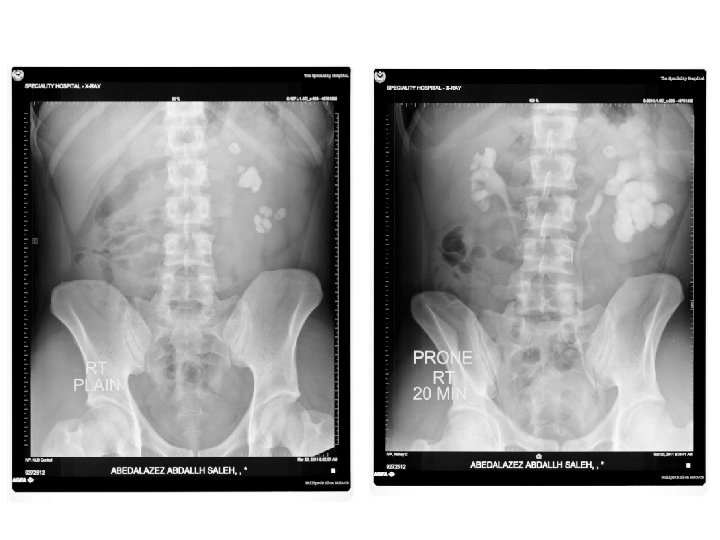

IVU • Conventional x-ray plus intravenous contrast. • Cheap. • Recently replaced by CT and MRI. • Useful for radioopaque stones.

IVU Image features: • Projectional image. • Image contrast determined by tissue density and IV contrast. • Good evaluation of collecting system and radio-opaque stones.